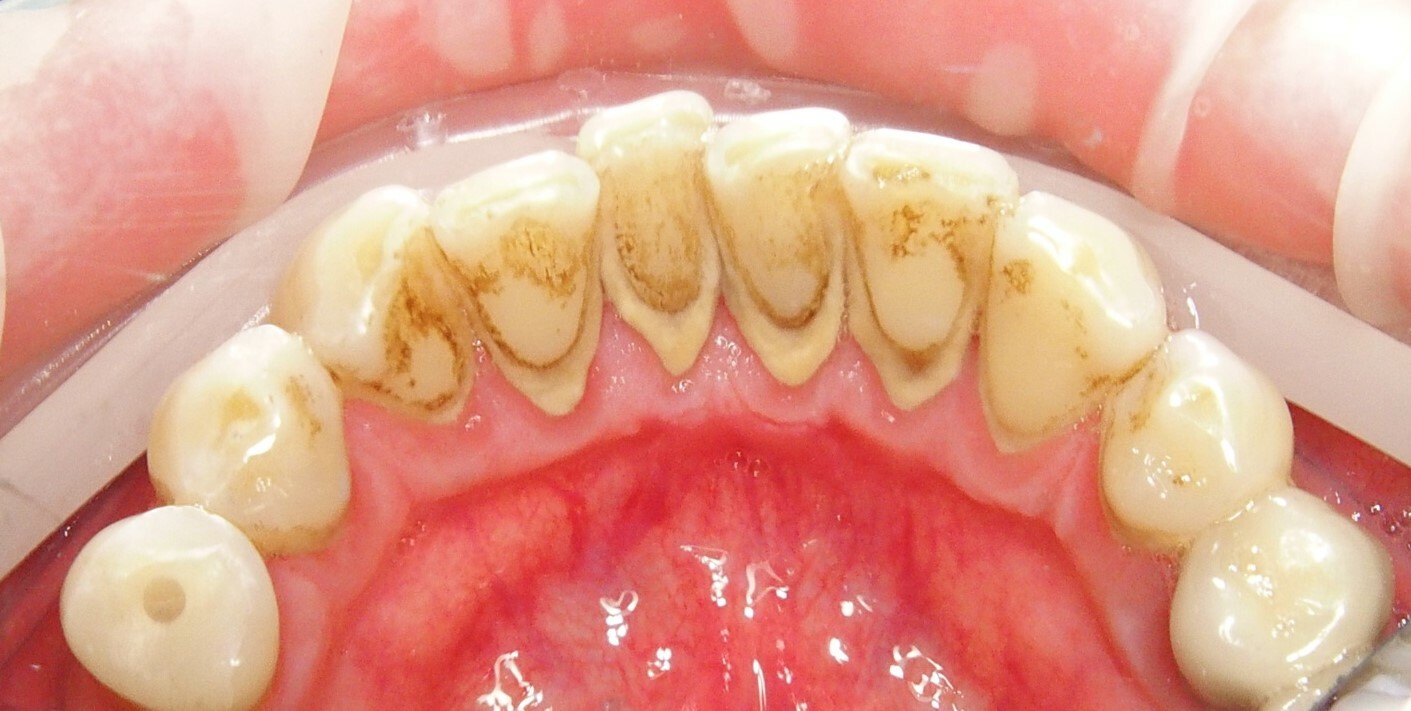

ПОКАЗАНИЯ

Твердый/мягкий зубной налет

Удаление зубного камня с

помощью ультразвукового

наконечника